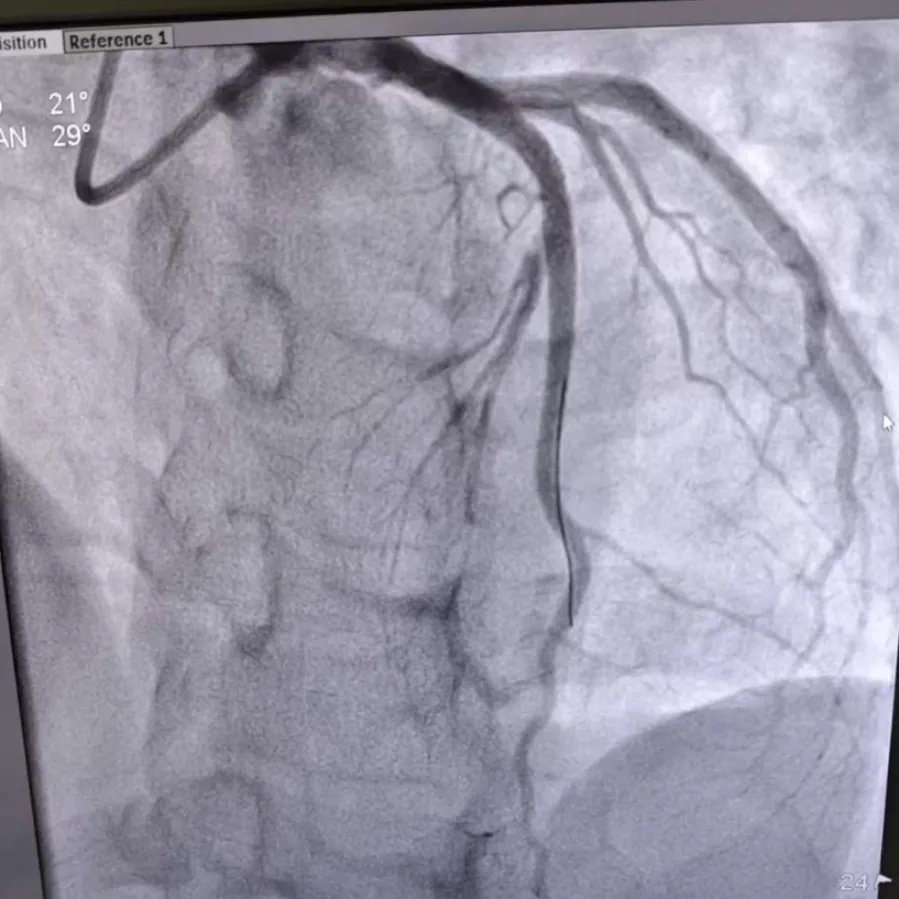

术后造影

面对万分危急的情况,心血管内科团队争分夺秒,通过血栓抽吸术清除“堵塞”,精准植入支架,及时打通了闭塞的血管。

随着血管的畅通,林先生的胸痛症状迅速缓解。